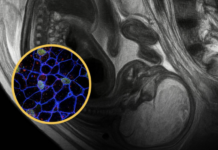

Çrregullime të gjakderdhjes

Shafrani i Indisë mund të ngadalësojë aftësinë e gjakut tuaj për t’u mpiksur, gjë që mund të intensifikojë problemet e gjakderdhjes.

Në të njëjtën mënyrë, ai mund të përforcojë gjithashtu efektet e ilaçeve për hollimin e gjakut, të cilat mund të rrisin rrezikun e gjakderdhjes.